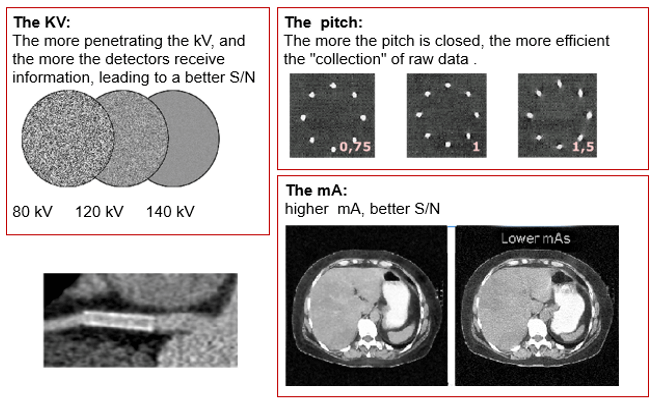

Improvement of S/N

The improvement of the signal to noise ratio can be accomplished in the following manner: the more penetrating the kV, and the more detectors receiving information; the higher the mA, the better the signal to noise ratio, and the more the pitch is “closed” the more efficient the collection of raw data.

kVp

Increasing the kVp will improve the signal to noise ratio. This increase in beam intensity allows for better penetration of denser objects.

mA

The signal-to-noise ratio in CT roughly follows the same principles as those of plain radiographs. It is calculated by comparing the level of the desired signal to the background deviation from normal pixel values. In general, the larger the number of photons transmitted, the greater the SNR.

In CT, the signal-to-noise ratio is determined by mAs-the greater mAs increases the SNR.

Remember, a lower signal-to-noise ratio generally results in a grainy appearance to images. AN underexposed CT image presents a noisy appearance due to the insufficient number of photons reaching the detectors.